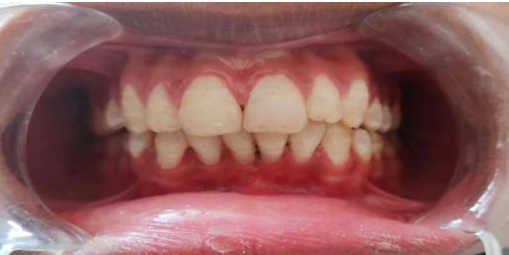

Figure 1 a, Figure 1b

Lingual aspects of the teeth were spot etched using 37% phosphoric acid gel for 30 seconds (VISTA VIS- 502115 Best-Etch Dentsply), rinsed off with air-water spray for 10 seconds and then air-dried. A thin layer of bonding agent (Prime & Bond NT Dentsply) was applied on the etched surfaces as per the manufacturer’s instructions. The splint was secured with light curing resin composite (Spectrum Dentsply) with 30 seconds of photopolymerization (Figure 1a). Once the splinting with composite and wire was performed, the patient was counselled and an intraoral periapical radiograph was taken to evaluate the tooth repositioning . The splint was evaluated for its stability, mobility, premature contact and comfort to the patient. The patient was given antibiotics (Amoxicillin 500 mg for every eight hours a day for seven days and Metronidazole 400 mg for every eight hours a day for seven days) to prevent infection as chance of spread of infection due to higher vascularization. The analgesics (Ibuprofen 400 mg every eight hours a day for three days) was given to reduce pain and decrease inflammation for improving healing with 0.2% chlorhexidine gluconate rinse every 12 hours for 14 days as an antiplaque mouth rinse. Postoperative written instructions for the consumption of a soft diet, maintenance of regular oral hygiene, avoidance of direct trauma by mastication, oral habits and immature contact were given. The patient was recalled after one week and examined for the stability of the splint. Splint was

placed for four weeks with weekly evaluation. At end of four weeks, splint was removed (Figure 1 b) with diamond bur. After one year of continuous three months follow up, the patient referred in the Endodontics for further treatment. At two years of follow up, color, contour, position of gingiva was excellent, well maintained alveolar bone height (Figure 2) & the patient was completely satisfied with result obtained.